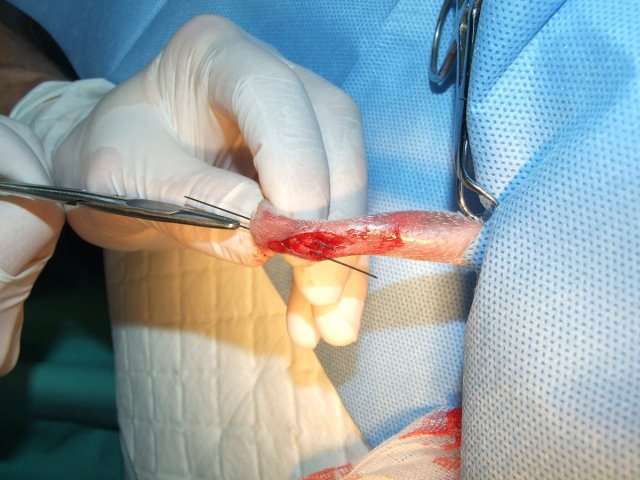

Velmi komplikovaná fraktura obou předloketních kostí u drobné činčily, jelikož se tak drobné implatáty běžně nevyrábějí, řešili jsme ji implantací nitrodřeňových hřebů vyrobených z injekčních jehel. Pacient se kompletně a bez následků uzdravil, po vyjmutí hřebů nožičku naplno používá.